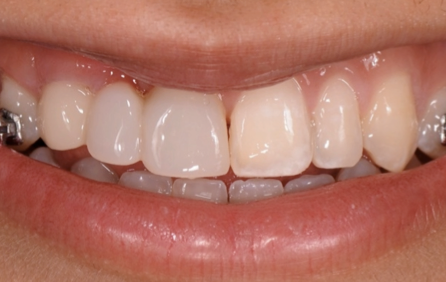

The patient had a congenitally missing upper right lateral incisor. Orthodontic treatment was performed to create the necessary space for a dental implant. Unfortunately, the implant failed, and so did several subsequent attempts to bone graft. These failures resulted in a visible smile deformity, that got worse after each failed procedure.

After the 3rd bone graft failed, the patient sought second opinions. She was a college sophomore at the time. Using a combination of interdisciplinary therapies, including S.M.A.R.T. minimally invasive bone grafting, Dr. Ernesto Lee was able to tridimensionally reconstruct this severe defect and place implants to restore the patient’s smile. The S.M.A.R.T. bone graft was also extended to treat adjacent teeth with thin/dehisced bone.

A long-term CAD/CAM fabricated temporary restoration is in place while she finishes medical school at an out-of-state university. The treatment of this case was published in detail in a special issue of the Compendium of Continuing Education in Dentistry, one of the largest circulation journals in our profession.